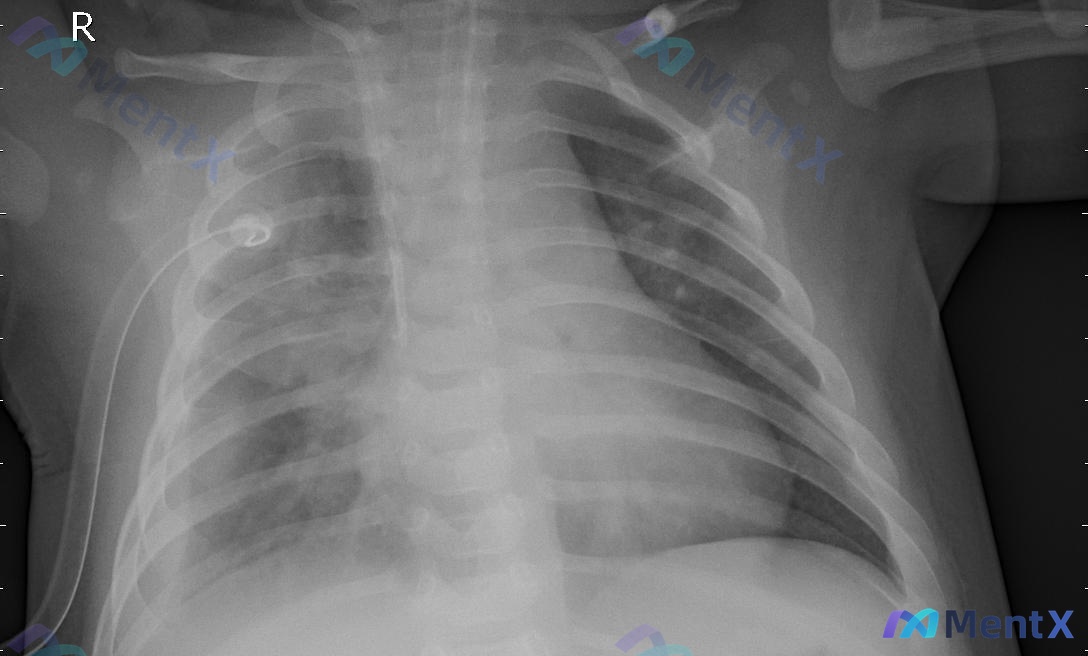

整理到一份卧位(AP位)的胸部X光资料,先不放后续,只看影像描述,大家第一步思路会怎么走? 已知影像事实: - 投照:卧位AP位,吸气一般,曝光尚可,有明显医疗器材伪影 - 器械:右侧胸壁可见带圆环状金属端的导管,横跨右肺野 - 肺野:右肺上中下野纹理粗,右肺门及内带可见斑片状密度增高影,边缘模糊,...